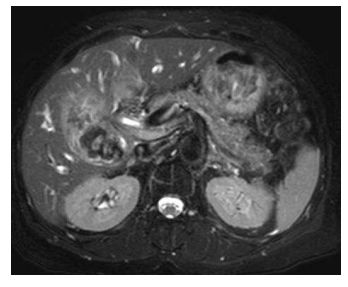

Uma paciente de 69 anos de idade, portadora de diabetes tipo 2, hipertensão arterial e hipotireoidismo, com história de IAM em 2017, apresenta quadro de icterícia progressiva, colúria, acolia, dor abdominal em hipocôndrio direito e perda ponderal de 5 kg no último mês, com inapetência e queda do estado geral. Aos exames, Hb 9 g/dL, leucócitos 12.000/mm3 , amilase 80 U/L, TGO 250, TGP 190, bilirrubina total 11 mg/dL, bilirrubina direta 9,5 mg/dL, fosfatase alcalina 320 mg/dL, gama GT 400 mg/dL e PCR 2,5 mg/dL. Ao exame físico, dor à palpação de epigástrio e hipocôndrio direito, sem DB. Realizou uma ultrassonografia de abdome, que mostrava dilação de vias intra e extra-hepáticas, com espessamento de vesícula biliar. Complementou a investigação com ressonância magnética. Mostrou a imagem a seguir.